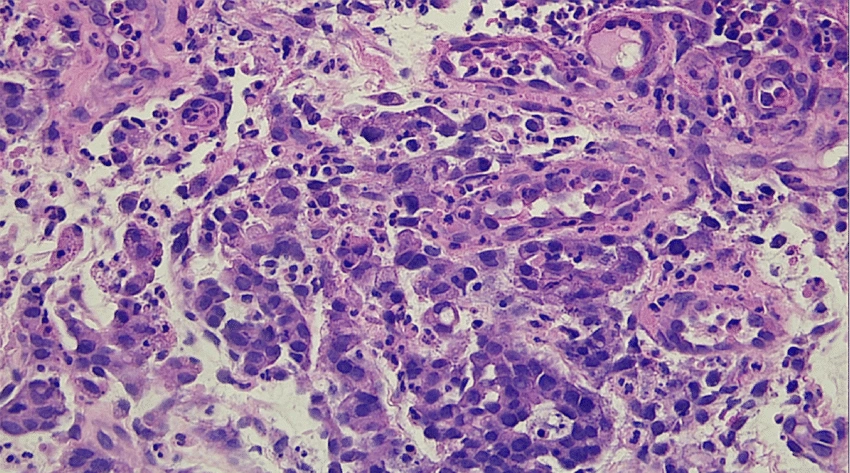

Аденокарцинома желудка (гистология)

Умеренно дифференцированная аденокарцинома желудка с подслизистой инвазией